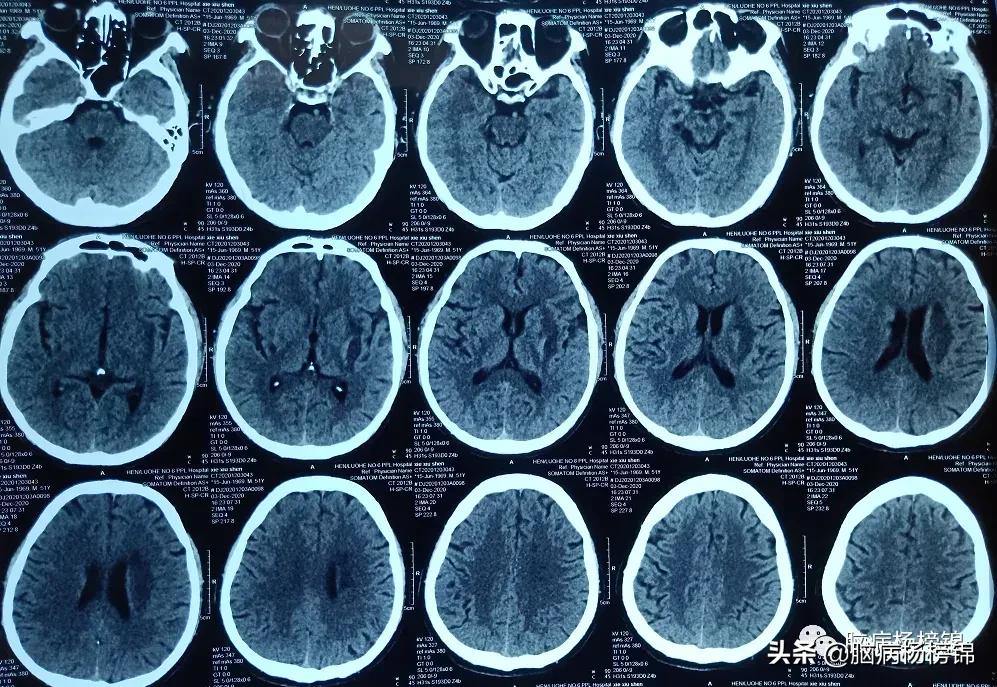

发病两个月的片子,遗留软化灶。